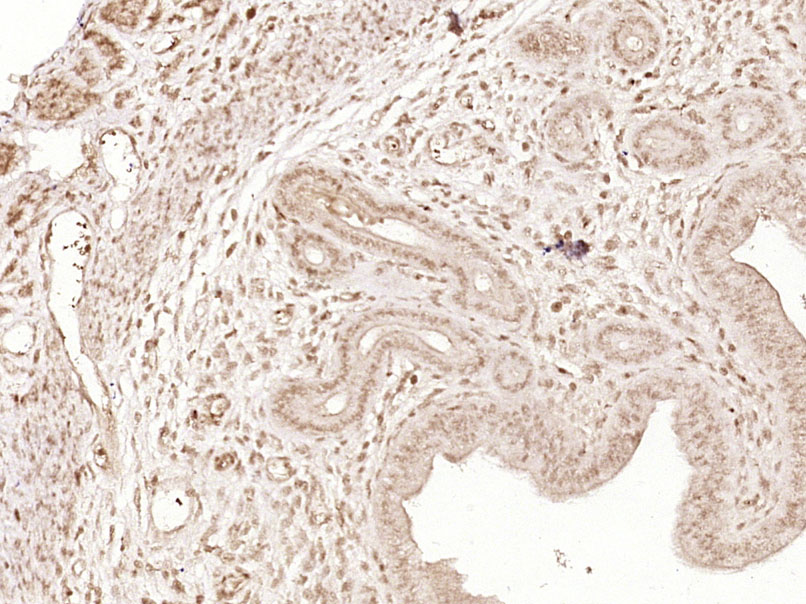

| 英文名称 | phospho-Paxillin (Tyr31) Rabbit pAb |

| 中文名称 | 磷酸化桩蛋白Paxillin抗体 |

| 产品应用 | IHC-P=1:100-500, IHC-F=1:100-500, IF=1:100-500 Not yet tested in other applications. |

| {IHC-P} | {1:100-500} |